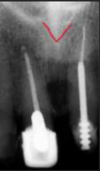

identify the anatomical structure below.

anterior nasal spine